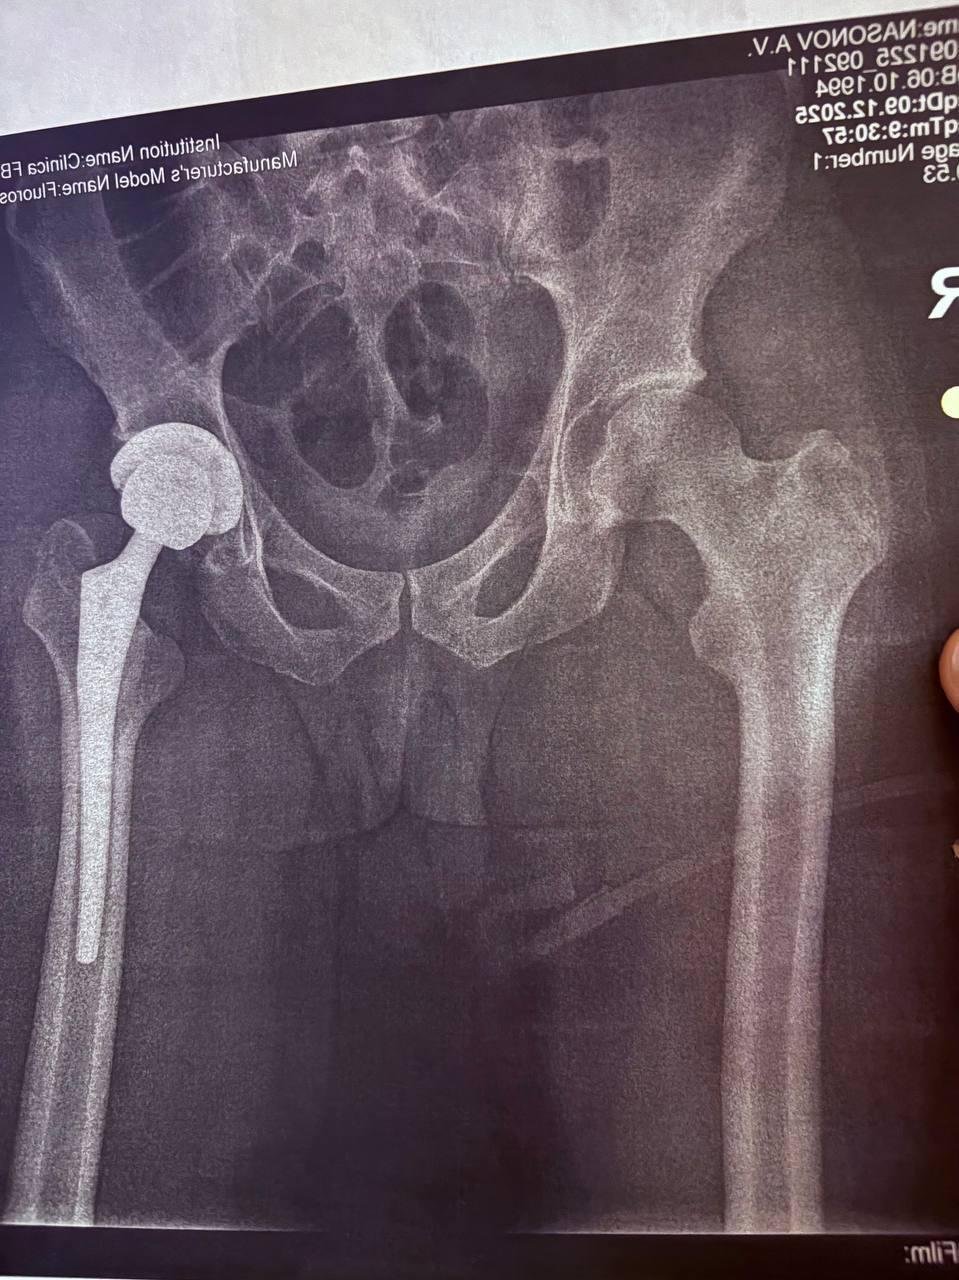

2. Операция по ОМС + сустав за свои деньги (мой вариант)

Если покупаешь сустав за свои деньги, то ждать не надо. Я был на приёме у врача 14 ноября, а 8 декабря мне уже делали операцию. Никуда ездить за суставом тоже не нужно. Врач сам связывается с поставщиком и даёт тебе контакты. Ты пишешь, тебе скидывают QR на оплату, затем присылают чек, а при выписке тоже дают гору бумаг о том, что тебе установили.

Я взял DePuy(Европа, бренд johnson & johnson) - по цене и словам врача это золотая середина, которой хватит на много лет, возможно даже навсегда, но тут много переменных.

Первые две недели было тяжеловато, так как можно двинуть ногой как-то не так, и она начнёт болеть. Из-за этого начинаешь её ещё больше беречь и стараться минимально ей шевелить. Дома первые две недели иногда пил обезбол, и ноге нужно много помогать, например, когда ложишься на кровать или если её нужно куда-то закинуть. Спустя 12 дней снял швы. Теперь нужно будет сделать рентген через два месяца.

Через четыре дня будет месяц с момента операции. С тростью хожу очень бодро. Самая большая проблема в том, что в 8–9 утра начинают болеть мышцы, и я просыпаюсь. Но это рабочий процесс, и нужно просто потерпеть. Думаю в силу возраста и остальных факторов реабилитация у меня идет очень быстро.

Даже сейчас вижу разницу что нога стала более подвижная (если сидя поворачивать ей влево\вправо) чем раньше и если выйти погулять то может быть дискомфорт из-за того что еще не все мышцы восстановились, но нет ощущения как раньше когда больная нога будто бы в 3 раза быстрее устает чем здоровая + может начать болеть сустав